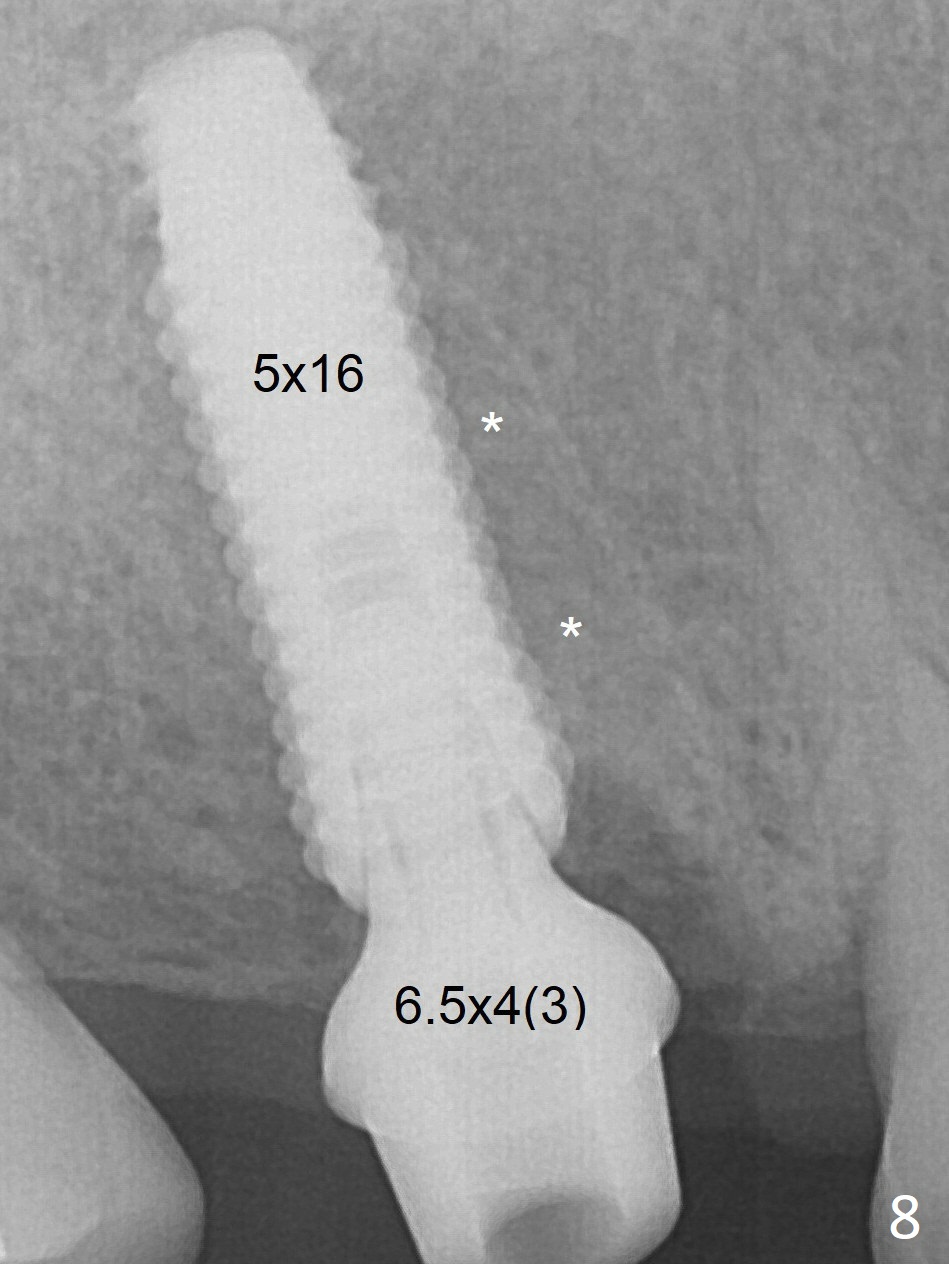

Implant immediately (Fig.8) and 2 months (Fig.12,13) post placement.